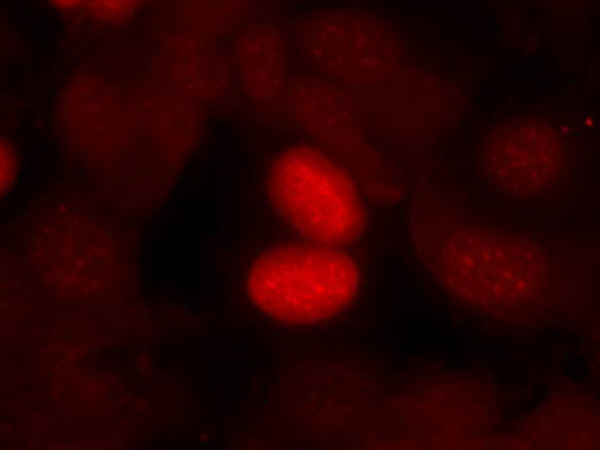

IF Positive control:

MCF7 cells

IF Recommended dilution

100-200